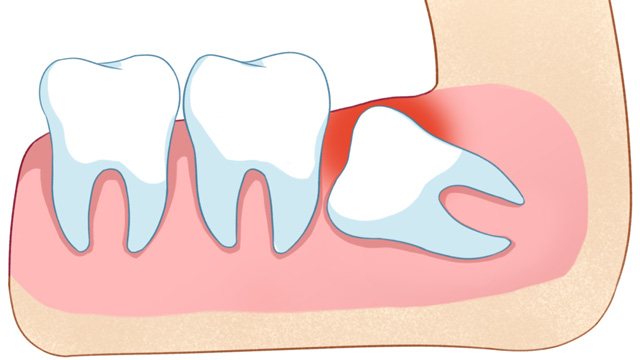

“医生,我拔完牙脸会不会肿?”“我看网上有人说肿得没法见人……”这几乎是每一位拔牙患者术前最担心的疑问。拔牙,尤其是拔除阻生智齿,过程堪比一场小型外科手术,术后肿胀确实是身体正常的炎症反应。但“肿成猪头”并非必然,关键在于术后48小时的黄金护理期,你做对了什么。今天,我们就为即将或刚刚完成拔牙的你,详细拆解一份科学、清晰的术后护理指南,帮你平稳度过恢复期,将肿胀和不适感降到最低。